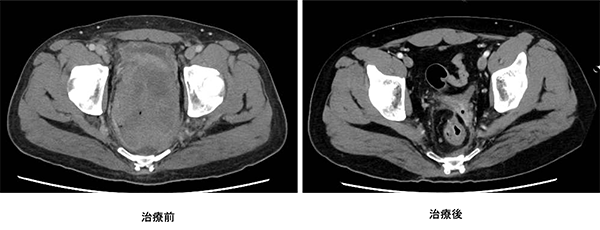

政府の「がん医療の均てん化政策(https://www.mhlw.go.jp/stf/shingi/other-kenkou_128568.html)により、多くの病院で良質ながん医療を受けることができるようになってきました。近年では、地域の拠点となる病院では、より高度で専門的ながん医療を行うことを目指した「がん医療の集約化」が重要視されています。そうした中、私達は本邦のガイドライン(https://www.jsccr.jp/guideline/index.html)だけではなく、欧米のガイドライン(https://www.nccn.org/guidelines/category_1)、(http://interactiveguidelines.esmo.org/esmo-web-app/toc/index.php?subjectAreaId=3&loadPdf=1)や大規模な臨床試験など、常に最新のがん治療にアンテナを張り、その時点で最良と思われる治療を提供できるように努めています。また、他の病院では手術ができないと言われたような場合や人工肛門が必要だと言われた場合でも、本当にできないのか、人工肛門を回避できる方法はないのかなど、内科や放射線科、病理診断科など、がんを専門とする複数の診療科とともに合同カンファレンスを行い、最適な治療法を常に模索しています(図1-5)。

ロボット支援下手術により安全に吻合できるようになったため人工肛門が回避できた。